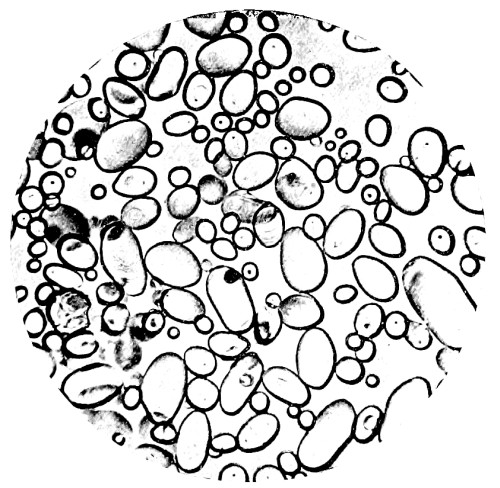

| 8. | Measurement of Blood Corpuscles (human) | 97 |

| 9. | Measurement of Blood Corpuscles (sheep) | 97 |

| 10. | Photo-micrograph of Red Blood Corpuscles from Domestic Fowl | 99 |

| 11. | Photo-micrograph of Blood Corpuscles of Fish | 99 |

| 12. | Photo-micrograph of Blood Corpuscles from a Dried Stain of the Blood of a Cod-fish | 100 |

| 13. | Photo-micrograph of a Frog‘s Blood showing oval nucleated Red Corpuscles | 101 |

| 14. | Photo-micrograph of Crystals of Hæmin | 102 |